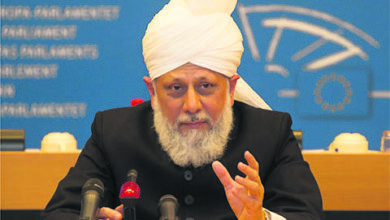

جان بچانے کےلیے انسانی جسم میں سؤر کے دل کی ٹرانسپلانٹیشن کرنےکی ممانعت نہیں

سوال: ایک دوست نے حضور انور ایدہ اللہ تعالیٰ بنصرہ العزیز کی خدمت اقدس میں لکھا کہ حال ہی میں…

کیاکورونا وائرس کے ختم ہونے کے بعد دنیا معمول پرآسکتی ہے؟

سوال: اسی Virtual ملاقات مورخہ 29؍نومبر 2020ء میں ایک اور طفل نے حضورانور کی خدمت اقدس میں عرض کیا کہ…

کیاکورونا وائرس کی ویکسینیشن کروانی چاہیے؟

سوال:حضور انور ایدہ اللہ تعالیٰ بنصرہ العزیز کے ساتھ اطفال الاحمدیہ جرمنی کی Virtual ملاقات مورخہ 29؍نومبر 2020ء میں ایک…

کیا خون اور مرنے کے بعد جسمانی اعضاء Donateکیے جا سکتے ہیں؟

سوال: حضور انور ایدہ اللہ تعالیٰ بنصرہ العزیز کے ساتھ کینیڈا کے اطفال کی Virtual ملاقات مورخہ 15؍اگست 2020ء میں…